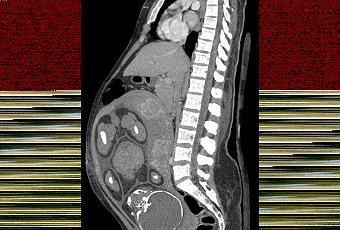

Tomographie par contraste de phase d'une grossesse de 37 semaines.

Source: https://en.wikipedia.org/wiki/Medical_imaging_in_pregnancy